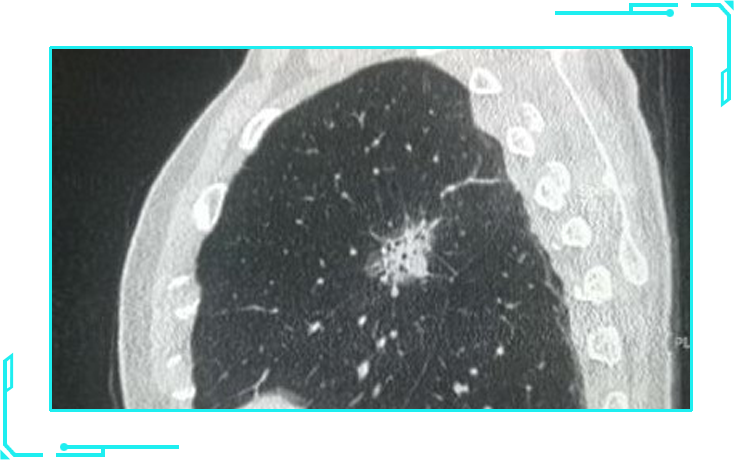

随着CT等影像检查的进步,越来越多的人在体检时被发现存在肺结节,因为担心肺结节转变成癌,很多人对这些结节一直提心吊胆。哪种肺结节最易转变成肺癌?今天,小编就带领大家,深度了解肺结节的分类!

在薄层CT上,根据肺结节的密度大小,将肺结节分为以下三种:

纯实性结节

纯实性结节类似于单独分离的蛋黄,是一个实性且密度较高的病灶。

肺结节薄层CT(首选)

肺结节薄层CT是放射科专门针对肺结节开设的检查项目,层距小于2mm,对肺结节的分辨率更高,还可以精确测定结节的密度,通过三维重建可精确测量结节的体积、与血管的关系、边缘等,有利于良恶性的判断,可用于肺结节的明确诊断及随访检查。